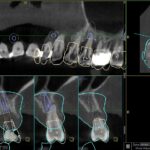

ΨΗΦΙΑΚΗ ΤΟΠΟΘΕΤΗΣΗ ΕΜΦΥΤΕΥΜΑΤΩΝ

Η ακρίβεια είναι πολύ σημαντική για την επιτυχία ενός εμφυτεύματος και μέσω του ψηφιακής τοποθέτησης μπορούμε να πετύχουμε το απόλυτο. Ο χειρουργός σας καθορίζει ψηφιακά σε ποια θέση πρέπει να μπει ένα εμφύτευμα και με τη χρήση ενός εξατομικευμένου νάρθηκα επιτυγχάνει το ιδανικότερο αποτέλεσμα. Λιγότερος χρόνος, λιγότερος πόνος, τέλεια αποκατάσταση!